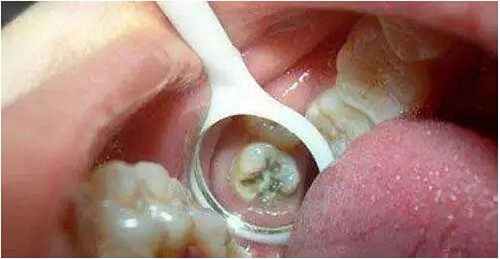

*牙髓炎:深齲由于齲洞離牙髓比較近,齲洞內(nèi)的細(xì)菌和細(xì)菌所產(chǎn)生的毒素容易滲透到牙髓組織,引起牙髓炎,使患牙發(fā)生劇烈疼痛。這個(gè)階段,根管治療是唯一可行的辦法。治療時(shí)需要麻醉后將牙髓組織清除,即大家所說(shuō)的“殺神經(jīng)”。

*根尖炎:牙髓炎得不到及時(shí)治療,或治療不徹底,細(xì)菌可通過(guò)牙髓向根尖擴(kuò)散,引起牙齒根尖部的病變,如根尖炎、根尖周炎、根尖膿腫等不同疾病。根尖部的病變急性發(fā)作時(shí)也會(huì)引起較重的疼痛,甚至牙齦及面部腫脹。根尖炎也需要行根管治療。

2.jpg

牙齒神經(jīng)因各種原因而導(dǎo)致壞死,并在沒(méi)有經(jīng)過(guò)治療,清除壞死的牙神經(jīng)時(shí),致病菌繼續(xù)往下發(fā)展至牙根根尖周組織。導(dǎo)致根尖部牙周內(nèi)血管擴(kuò)張,充血,局部組織呈現(xiàn)水腫,此時(shí)患牙可由初期的不舒服,發(fā)木,浮出發(fā)脹,伸長(zhǎng)感,與對(duì)合牙咬有疼痛感。當(dāng)病變繼續(xù)發(fā)展,根尖周膜內(nèi)滲出物增多,牙周間隙內(nèi)壓力升高,患牙浮出或伸長(zhǎng)的感覺(jué)逐漸加重,患者可明顯感覺(jué)牙齒有松動(dòng),并出現(xiàn)自發(fā)性,持續(xù)的鈍痛,與對(duì)合牙咬合壓力增加了根尖部組織的負(fù)擔(dān),刺激了神經(jīng),引起更為劇烈的疼痛,患者不愿咀嚼,影響進(jìn)食。此時(shí)是牙齒根尖周炎的早期病變,也稱漿液性根尖周炎,炎癥繼續(xù)發(fā)展,則發(fā)生化膿性變化。炎癥進(jìn)入根尖孔附近的牙槽骨髓腔中,并迅速在牙槽骨內(nèi)蔓延,膿液穿過(guò)骨松質(zhì)內(nèi),到骨外板(骨密質(zhì)),達(dá)骨膜下,由于骨膜堅(jiān)韌,致密,不易穿破,膿液在此處積聚,造成局部壓力增高。同側(cè)頜下淋巴結(jié)或頦下淋巴結(jié)可有腫大及壓痛,牙齒的疼痛可達(dá)到整個(gè)病變期高峰,病程在此時(shí),已是牙槽骨的局限性骨髓炎,嚴(yán)重時(shí)還將發(fā)展為頜骨骨髓炎或并發(fā)頜面部間隙感染。由于根尖周炎,是牙齒外部的炎癥,所以治療的難度都要比牙齒內(nèi)部的炎癥(牙髓炎)更大,時(shí)間更久。??